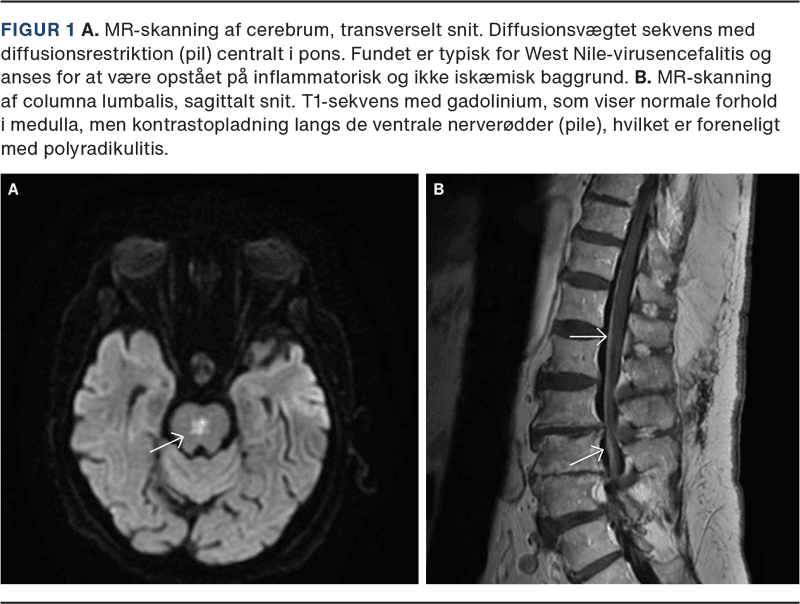

Patienten udviklede hurtigt slap tetraplegi og forblev komatøs. En MR-skanning af hjernen viste en inflammatorisk forandring i pons (Figur 1 A). En nerveledningsundersøgelse viste betydeligt tab af motoriske forhornsceller, og en MR-skanning af ryggen var med kontrastopladning langs de ventrale nerverødder (Figur 1 B). Fundene var forenelige med WNV-induceret encefalomyeloradikulitis.